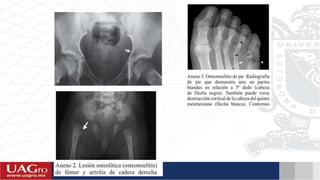

ESTUDIOS RADIOGRAFICOS

• Pueden ser normales o mostrar sólo aumento de volumen de

tejidos blandos los primeros días

• Solicitar proyecciones AP y LATERAL de la región afectada

DESPUES DE 10 DÍAS EMPIEZAN A

VISUALIZARSE CAMBIOS EN LA

RADIOGRAFÍA.

Reacción perióstica; se observa como

una pequeña nube

Necrosis ósea (secuestro); se observa

como pequeñas zonas aumentadas en